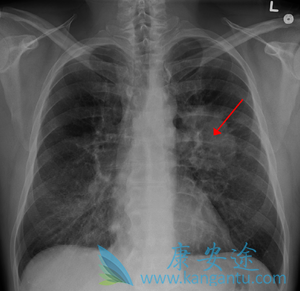

肺癌中晚期能活多久 ,没有一个特定的日期,但是只要选对方法,就一定能争取肺癌的生存期方面取得一定的成效。      最近,不时有报道称,哪个明星又得 肺癌 死了,在所有的肿瘤疾病中,肺癌的发生最常见,不过很多肺癌患者最关心的莫过于自己能活 ...

伽马刀治疗肺癌 目的是通过精确的定位和周密的放疗计划,最大程度的照射肿瘤,最好的保护肿瘤周围正常组织,从而更好的控制肿瘤,减少放射损伤。目前临床肺癌治疗综合放疗技术,特别是伽马刀是较常用的治疗方法。本文主要就体部伽马刀的治疗原理、剂量 ...

肺癌患者发展到了肺癌晚期还有救吗

肺癌患者确诊为晚期,患者和家属急切想知道,治疗情况如何? 肺癌晚期还有救吗 ?虽说癌症目前还不能达到完全治愈,但仍有不少晚期 肺癌 患者带瘤生存,治疗效果不错,生活质量也很高的案例。肿瘤不止手术切除、放化疗、中医治疗等方法,由于病由心生,患 ...